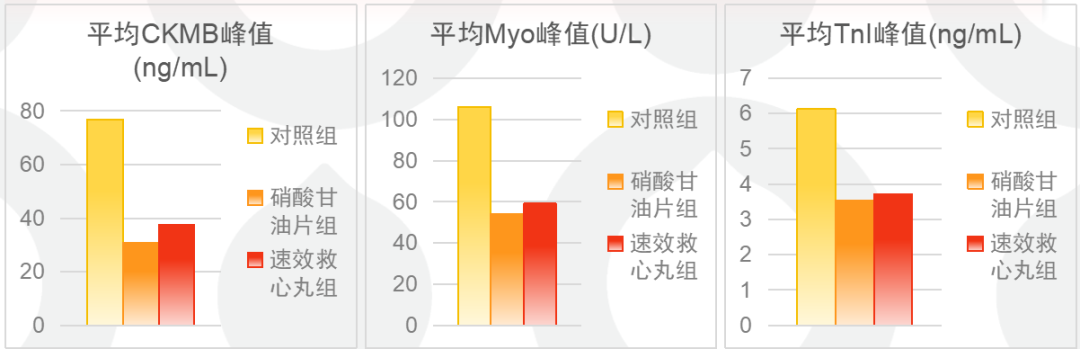

梗死面积控制与硝酸甘油等效

一项纳入318 例 STEMI 患者的临床研究表明,院前服用速效救心丸者,以肌酸激酶 MB(CKMB)、肌红蛋白(Myo)、血清肌钙白 I(TnI)峰值评估的梗死面积,与硝酸甘油组无差异(如下图)。表明在入院前使用速效救心丸,疗效与硝酸甘油片类似,作用快速而显著。证实速效救心丸可作为硝酸甘油片代替药物,用于急性心肌梗死患者的入院前急救治疗,且不增加主要心血管事件风险。